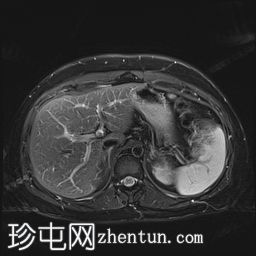

轴位T1加权像

同相位序列

T1低信号,T2低信号为主的脾脏肿块,内部可见T2高信号分隔,呈进行性强化。肿块中央可见星状瘢痕。

脾脏硬化性血管瘤样结节性转化(SANT),9.8 cm肿块

顾名思义,脾脏硬化性血管瘤样结节性转化(SANT)是一种纤维性血管病变。本病例展示了SANT的一些典型影像学特征,包括边界清晰的病灶,中央可见瘢痕,以及呈放射状进行性强化。这些特征使得术前MRI诊断较为明确。尽管SANT是一种良性病变,但大多数患者仍需行脾切除术以明确病理诊断。